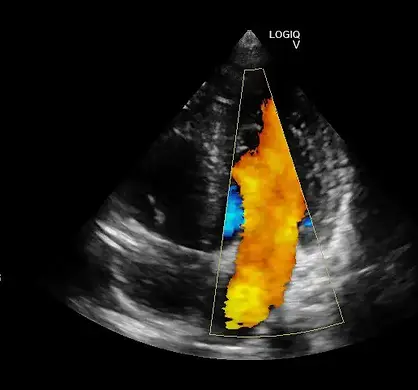

O Doppler Colorido

Durante o ultrassom, o médico avalia o fluxo de sangue nos vasos, verifica a formação de placas de gordura, estreitamentos, trombose, varizes, e a diminuição na irrigação de órgãos e estruturas importantes.